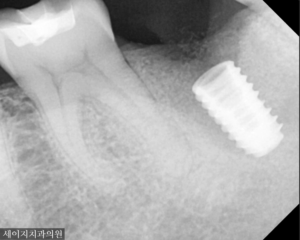

정확하게 식립하기 위해서 원칙적인 식립 위치의 첫 임플란트 드릴 각도를 봅니다. 빠르게 심는 것은 누구나 할 수 있지만, 바르게 심는 것은 정성과 열정이라고 생각합니다. 하나의 임플란트를 심더라도 오래토록 건강하게 사용하였으면 하는 마음으로 세이지치과는 안전하고 바르게 식립하고 있습니다.

임플란트 식립 후, 임플란트의 인공나사와 뼈가 붙는 시간을 약 3개월 간 기다려 최종 보철물을 장착 해드렸습니다.